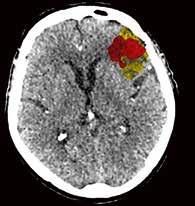

jedes einzelne Pixel. Die Software stellt sogar selbstständig fest, ob die Untersuchung mit oder ohne Kontrastmittel durchgeführt wurde.“ Handelt es sich um eine Untersuchung ohne Kontrastmittel, sucht Auto-Stroke nach einer Gehirnblutung und erkennt selbstständig die unterschiedlichen Arten: subdural, epidural oder subarachnoidal. Wurde bei der Untersuchung Kontrastmittel verwendet, sucht die Maschine nach einem Gefäßverschluss. Und auch Perfusionsstudien werden automatisiert ausgewertet. Sowohl die ausgewerteten Bilder als auch die maschinell erstellten Reports werden direkt ins PACS geschickt. Man kann das System auch so einstellen, dass es den Report per E-Mail entweder an die behandelnden Ärzt*innen oder zusätzlich an die Radiolog*innen versendet. Im PDF-

Befundbericht sind in den Bildern die verdächtigen Areale markiert beziehungsweise farblich hervorgehoben, so dass leicht zu erkennen ist, wo eine Veränderung stattgefunden hat.

Automatisierte Befundberichte

▪ Für intrakranielle Blutungen

▪ Unterstützt die Erkennung mehrerer Varianten von Blutungen

▪ Benachrichtigt den Benutzer über das Vorhandensein einer DICOMBildausgabe, die das Vorhandensein einer potenziellen Blutung hervorhebt, und zeigt verdächtige Schichten an

Unterschiedliche Color-Maps mit eindeutigen Infarktzeichen der linken Hirnhälfte.

Eindeutige Visualisierung des Infarktkerns (rot) sowie der Penumbra (gelb). Zusätzlich werden die Volumina, das Mismatch Ratio und das Relative Mismatch dargestellt.